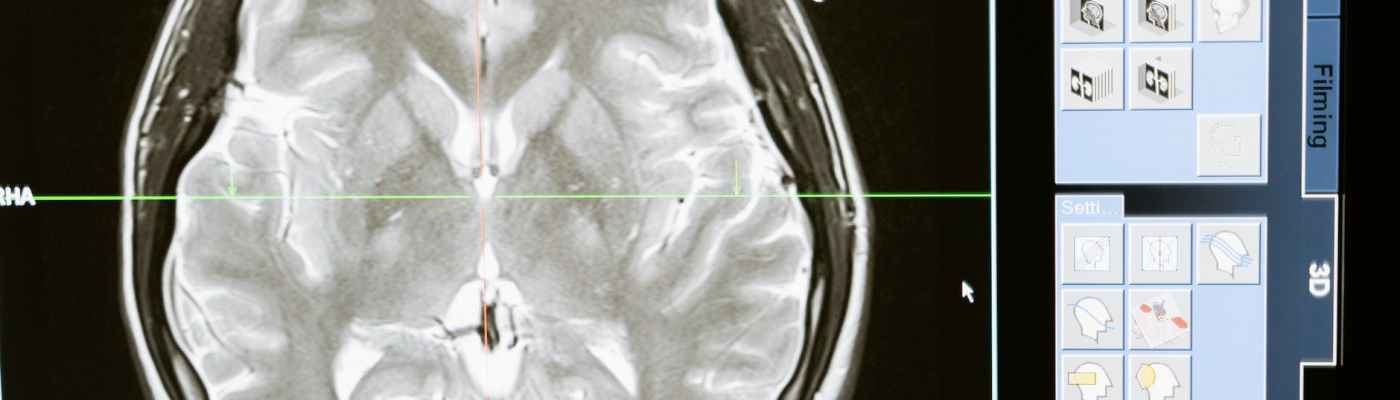

1. Functional Magnetic Resonance Imaging (fMRI): This method uses powerful magnets and radio waves to measure changes in blood oxygenation levels in different brain regions. It detects the blood oxygen level-dependent (BOLD) signal, which indirectly reflects neural activity.